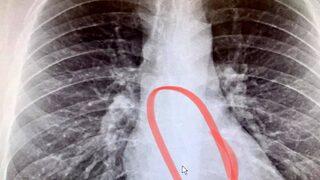

Boğaz kuruluğu nedeniyle doktora başvurdu, içinden kulaklık çıktı!

ABD'nin Massachusetts eyaletinde yaşayan Bradford Gauthier, sabah uyandığında boğazında kuruluk ve göğsünde ağrı hissetti. Gauthier soğuk algınlığı geçirdiğini düşünse de gerçek bambaşka çıktı.